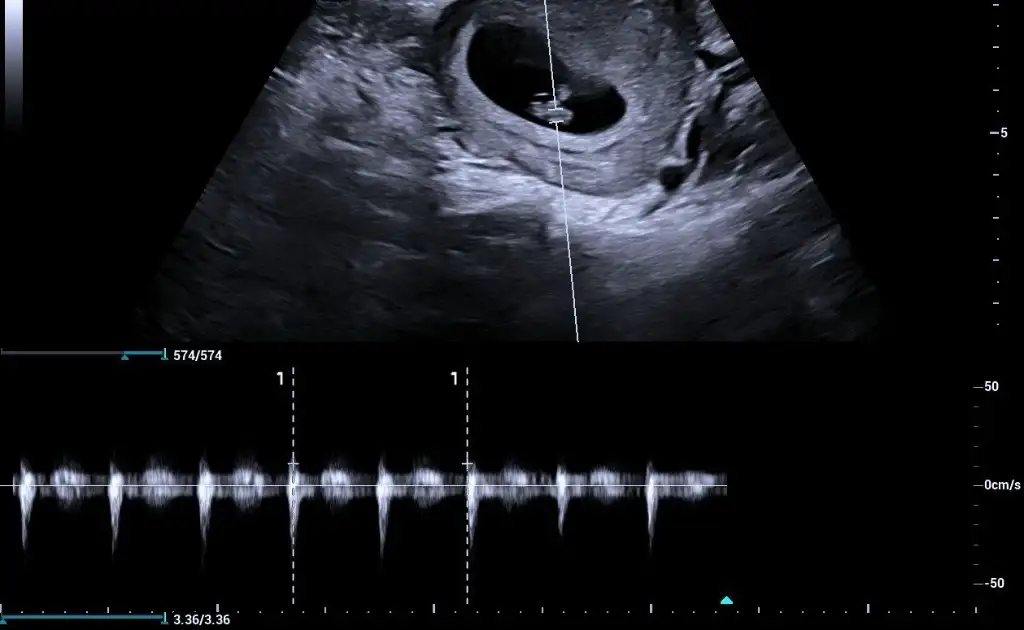

Kızlar benimkinide tahmin edin yaa kese yuvarlakmı ovalmi ben anlamıyorum burda 6+4 😂😂